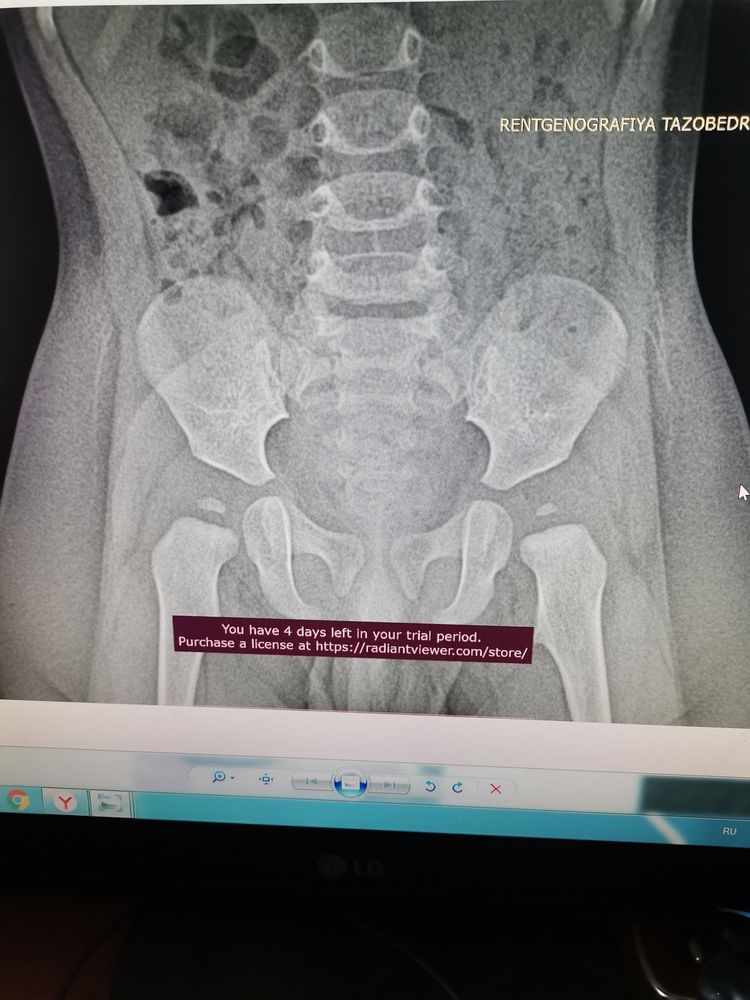

Мама Доченьки, вот такие результаты. Рентгенолог кагда заключение выдала, сказала что ортез не требуется. Массаж и физио достаточно. А врач настаивала на ортезе.